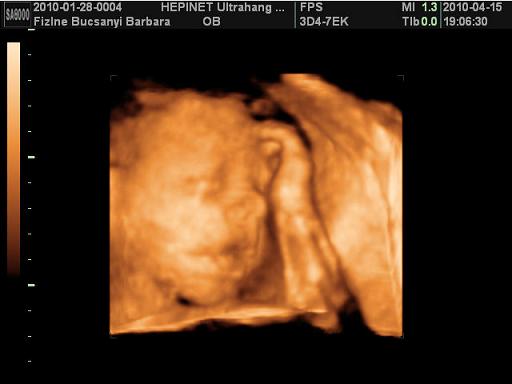

Kép Kép

nagyon klassz az ultrahangos kép, aranyos pofija van Kamillának, és milyen szép nevet választottatok, a második képen, mintha azt mondaná," na most már elég a fotózásból" :-)